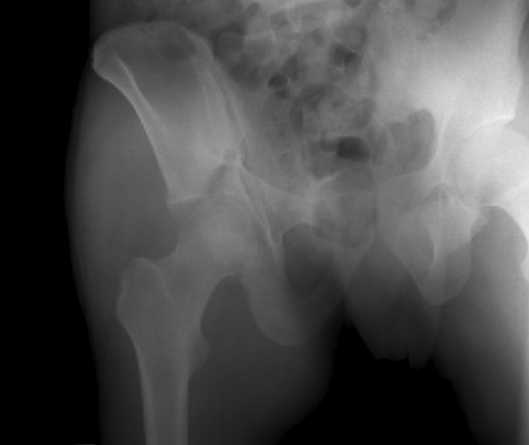

The details of the fracture are not so clear from the images sent...would you be able to send along an AP and Judet images as well as some additional axial images above and below the joint?

I’m not so sure that your patient has a Tr+PW pattern based on the images sent...maybe the fracture’s exact name won’t matter in the long run, but it’d be great to see enough images to make an accurate comment.

Without complete CT images and/or oblique radiographs, it's difficult to answer your question definitively, but it appears that there may not be a posterior wall fracture that requires a posterior approach. A successful reduction through an ilio-inguinal approach will have a faster recovery, and not risk SGN injury or heterotopic ossification.

Here are some more axial images. What is your opinion as for the timing of the operative treatment?